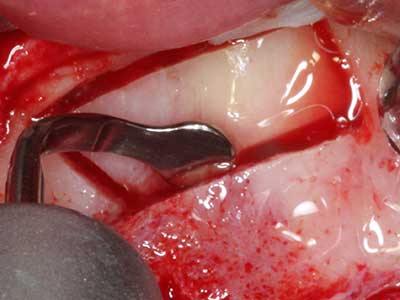

Fig. 18: Preparation of a cortical cover with the piezo bone saw (Piezomed, W&H).

Fig. 19: Surgical site after neurolysis and removal of osteoma.